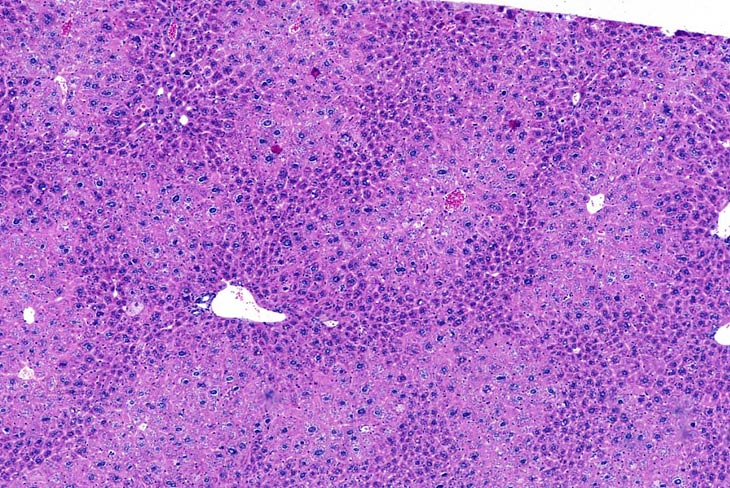

Centrilobular hepatocellular hypertrophy in a CD-1 mouse.

Centrilobular hepatocytomegaly (hypertrophy) in a mouse given phenobarbital for 8 months. Note the prominent eosinophilic cytoplasm reflective of smooth endoplasmic reticulum proliferation.